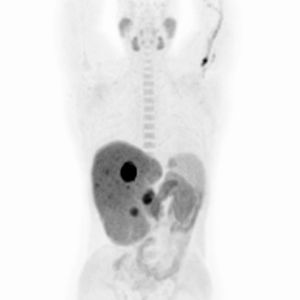

PET/CT vyšetrenie trupu s 18F-FDG

Široká škála onkologických aj neonkologických indikácií